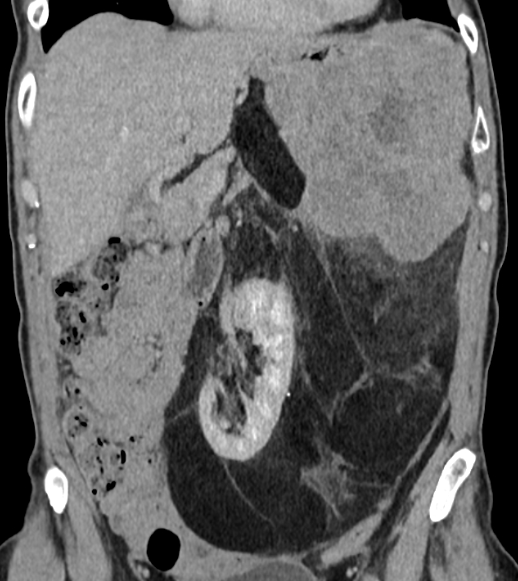

This patient has a dedifferentiated RPS, the biopsy was performed in the solid mass in the upper left abdomen. It's a high-grade liposarcoma, not metastatic.

However, as you can see, there is a considerable mass, which likely represents well differentiated sarcoma, reaching very far into the pelvis.

Neoadjuvant treatment is planned with chemo + RT, followed by surgery.

Would any of you consider

- to irradiate only the solid tumor component in the upper abdomen and ignore the rest

- to deliver a lower dose to the presumed well-differentiated component than in the solid component. This would resemble a bit the HR-CTV-approach, where higher doses are pursued at the projected resection margins and lower doses are accepted in non-critical areas, in order to reduce doses to OARs.

Published guidelines do not really distinguish this, and I understand that the risk of dedifferentiation is everywhere and not 100% corresponding to what we see on imaging. On the other hand, delivering 45-50 Gy to the entire extent of the tumor will be quite toxic.